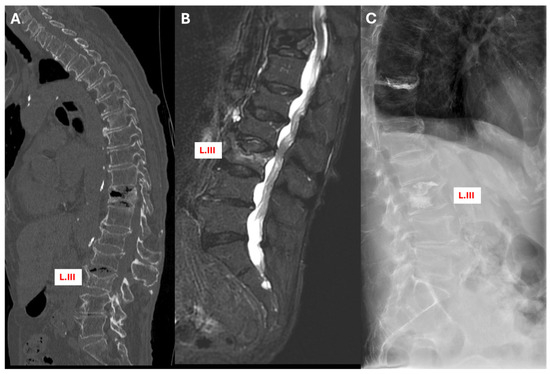

3.5.3. Case 3: Conversion from Conservative to Surgical Treatment